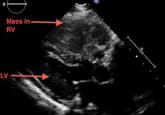

ArticleA large mass in the right ventricle: Tumor or thrombus?Author:Pradhum Ram, MDPublish date: July 1, 2017A 69-year-old woman with ovarian cancer presents with worsening dyspnea, lower-extremity edema, and dizziness.Read More